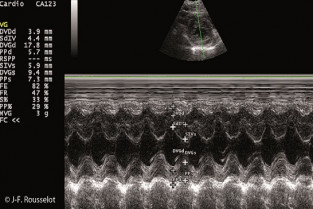

Le mode Temps Mouvement

Cours